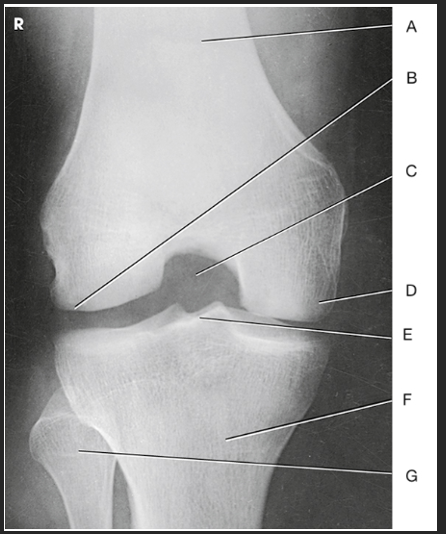

Name this projection

AP knee

Where does the CR enter for this projection?

½" inferior to patellar apex

If the patient is sthenic (19-24 cm) how is the CR directed?

0 degrees (perpendicular to IR)

Label the image: A

femur

Label the image: B

patella

Label the image: C

lateral femoral epicondyle

Label the image: D

lateral femoral condyle

Label the image: E

Lateral tibial plateau

Label the image: F

intercondylar eminence

Label the image: G

head of fibula